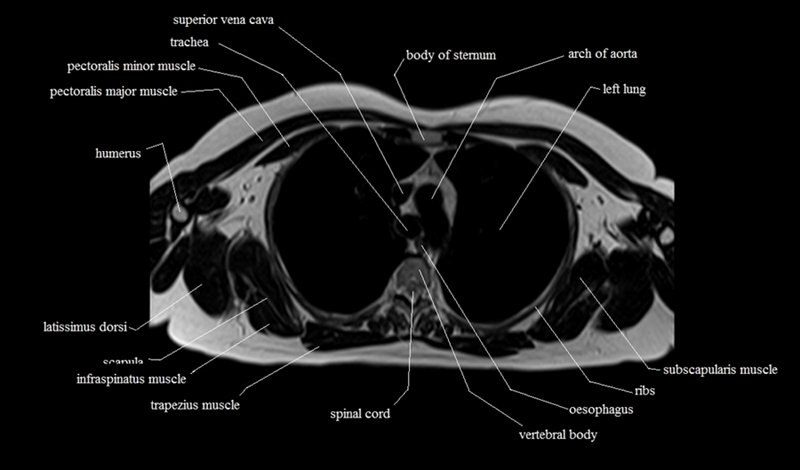

MRI Axial Cross Sectional Anatomy of Chest

This MRI chest (thorax) axial cross sectional anatomy tool is absolutely free to use. Use the mouse scroll wheel to move the images up and down, or alternatively, use the tiny arrows (→) on both sides of the image to navigate through the images. For a more detailed view, double-click the image to view it in full screen, and use the menu in the top right-hand corner to view individual slides or play them in a loop.